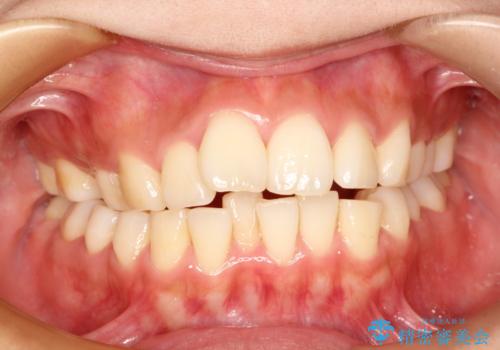

矯正治療が終わった後にクリーニング PMTC

担当医 歯科衛生士